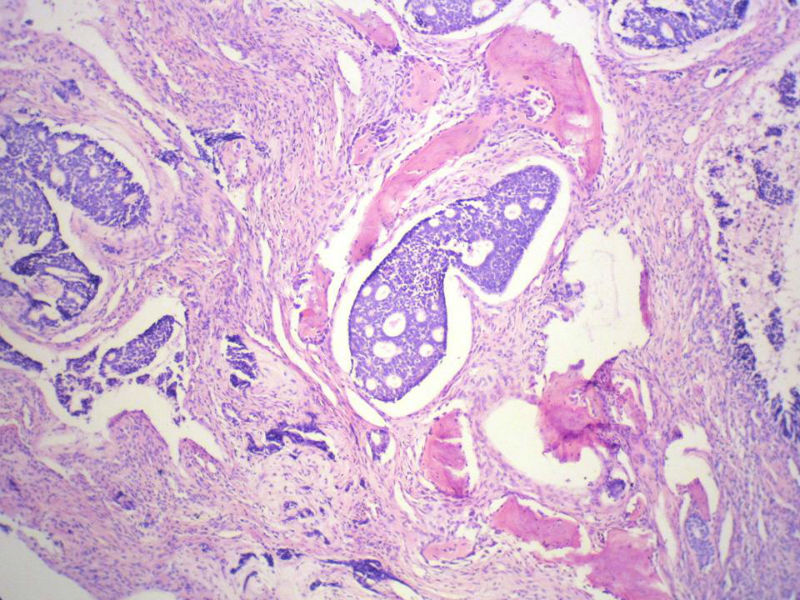

男,76岁,鼻塞两个月,CT提示左上颌窦占位,局部骨质破坏,口腔硬腭下降,局部活检。

腺样囊性癌,图像很典型的